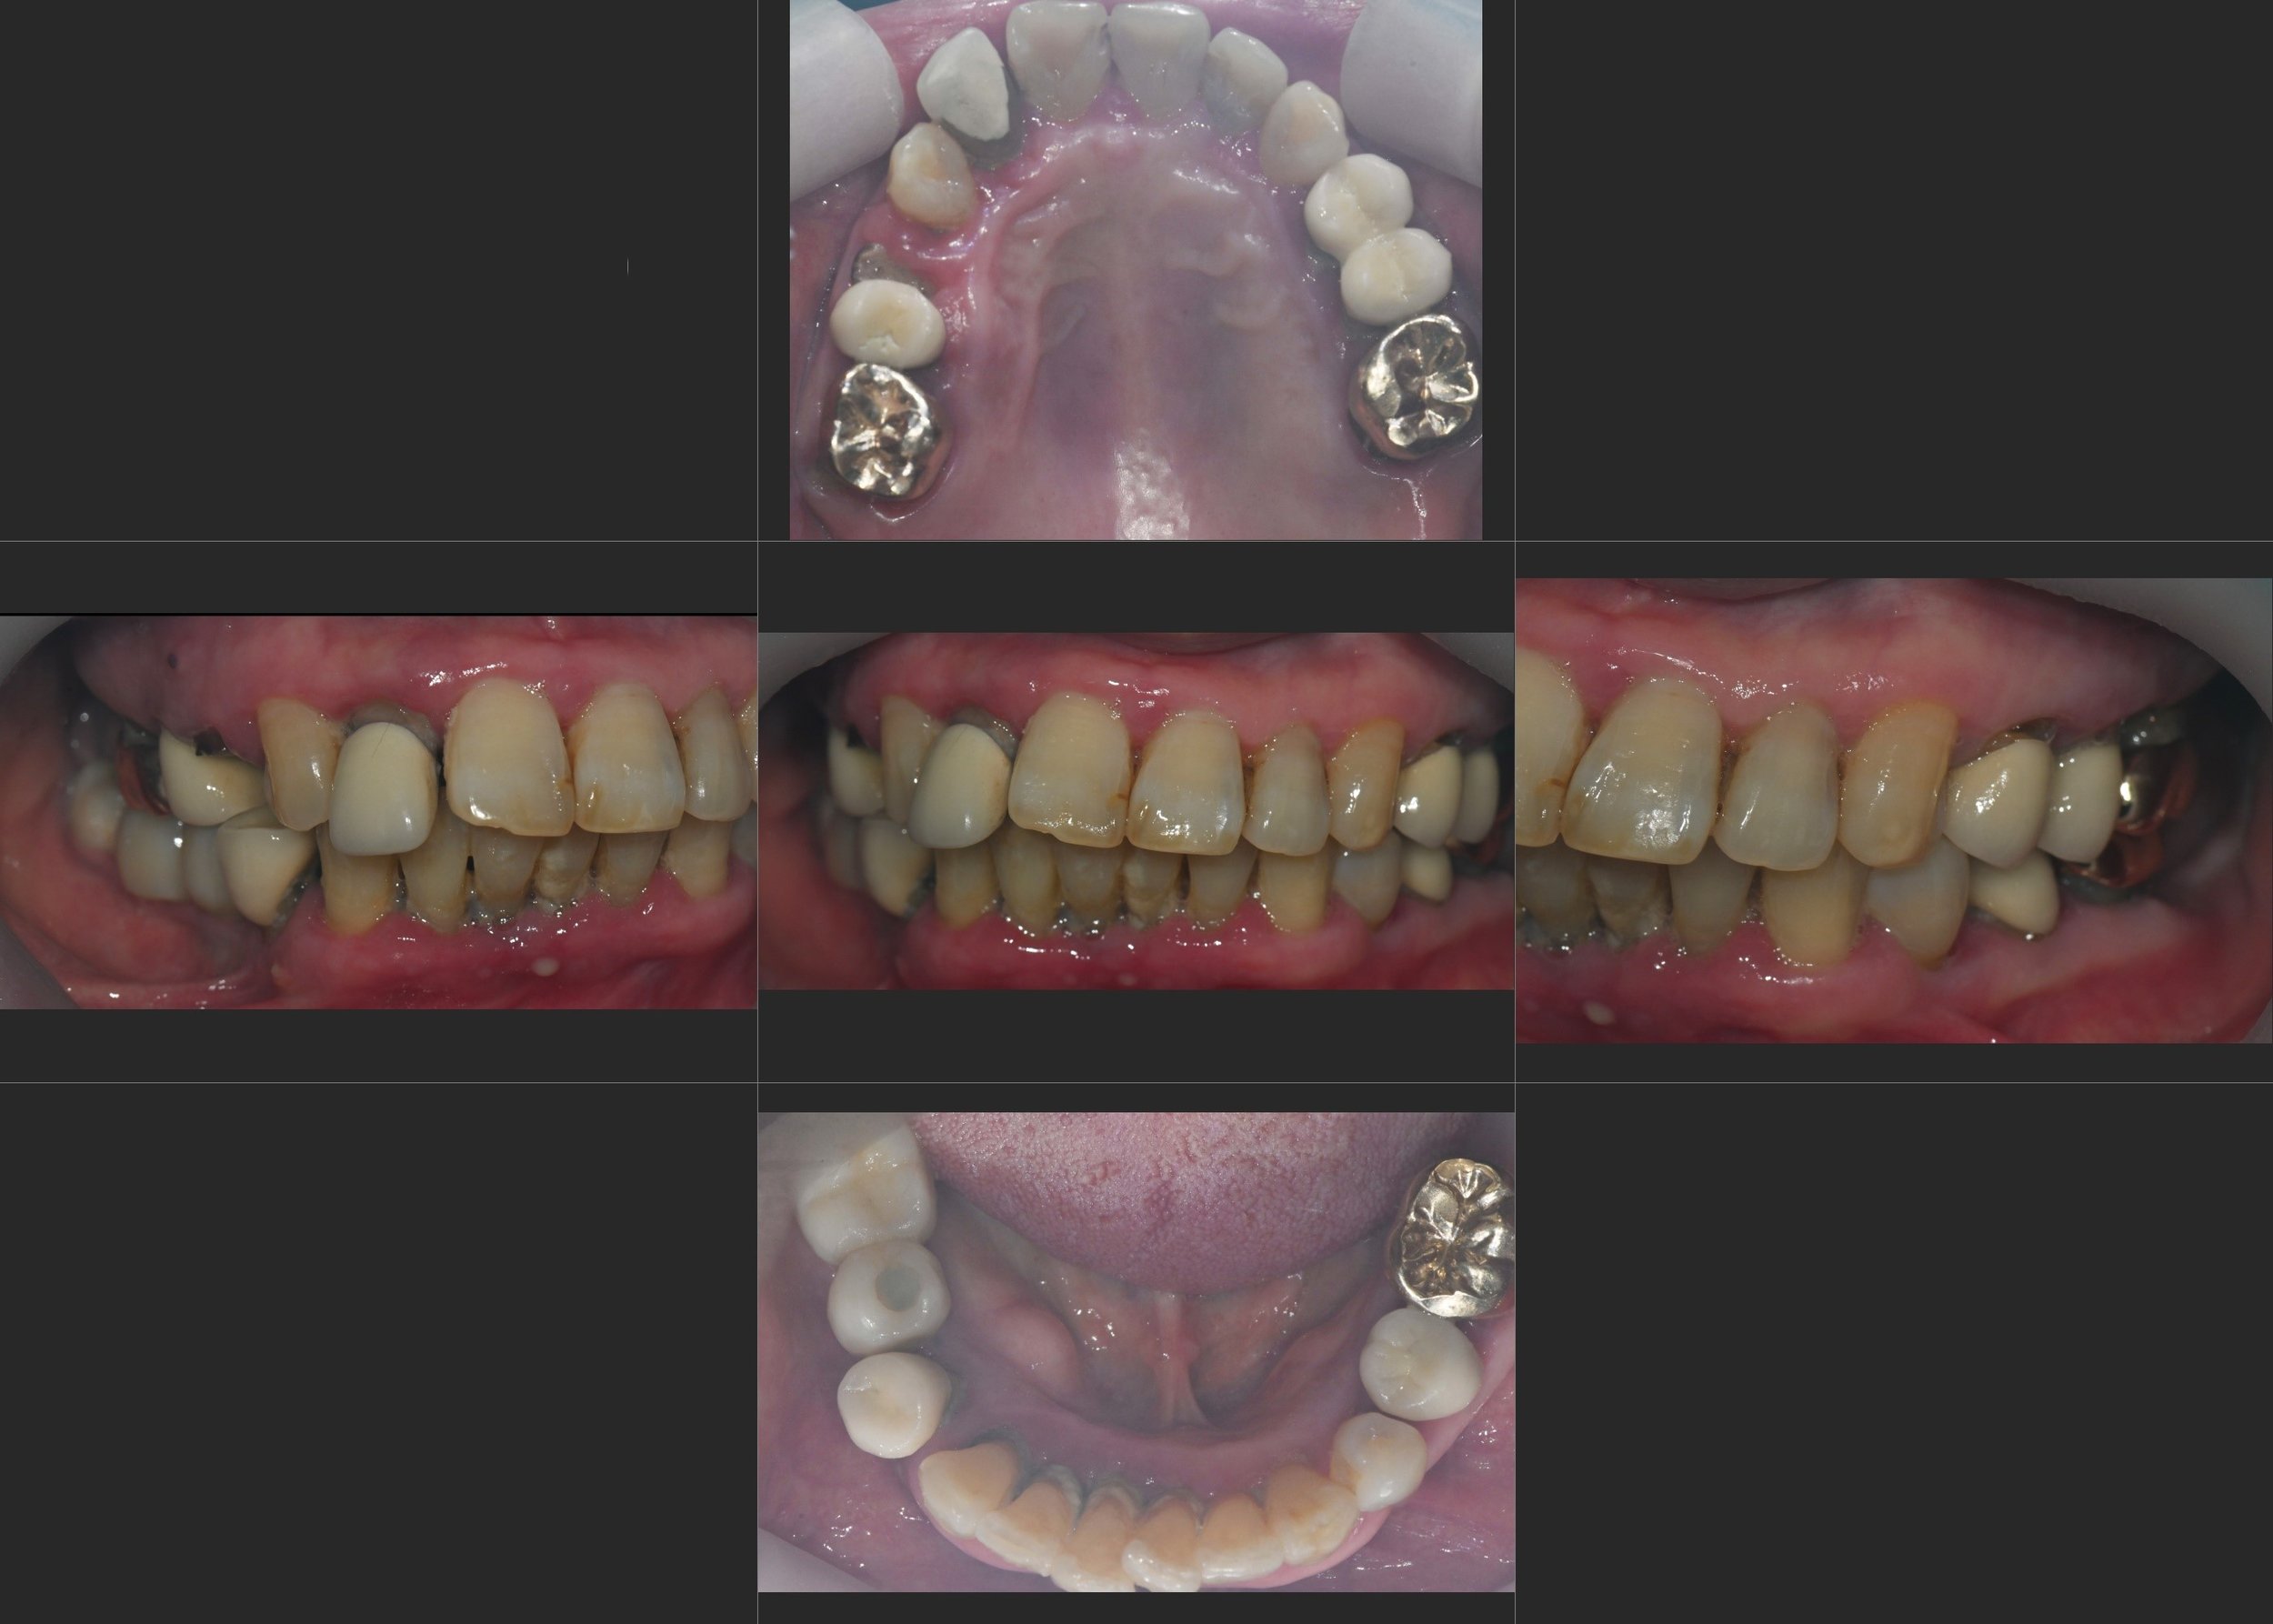

INTRA ORAL - AFTER

4. Final Definitive Delivery: Once functional stability and gingival health were verified, the final high-precision zirconia bridges and crowns were delivered. The result is a healthy, maintainable oral environment with a balanced occlusion and a naturally rejuvenated aesthetic profile.